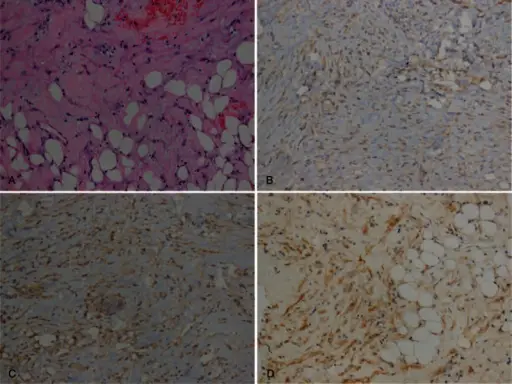

Angiomyolipoma

Angiomyolipoma is a disorder where benign kidney tumors develop.

Angiomyolipoma a tumor made up of blood vessels, smooth muscle, and adipose tissue.

Tuberous sclerosis is associated with angiomyolipoma.